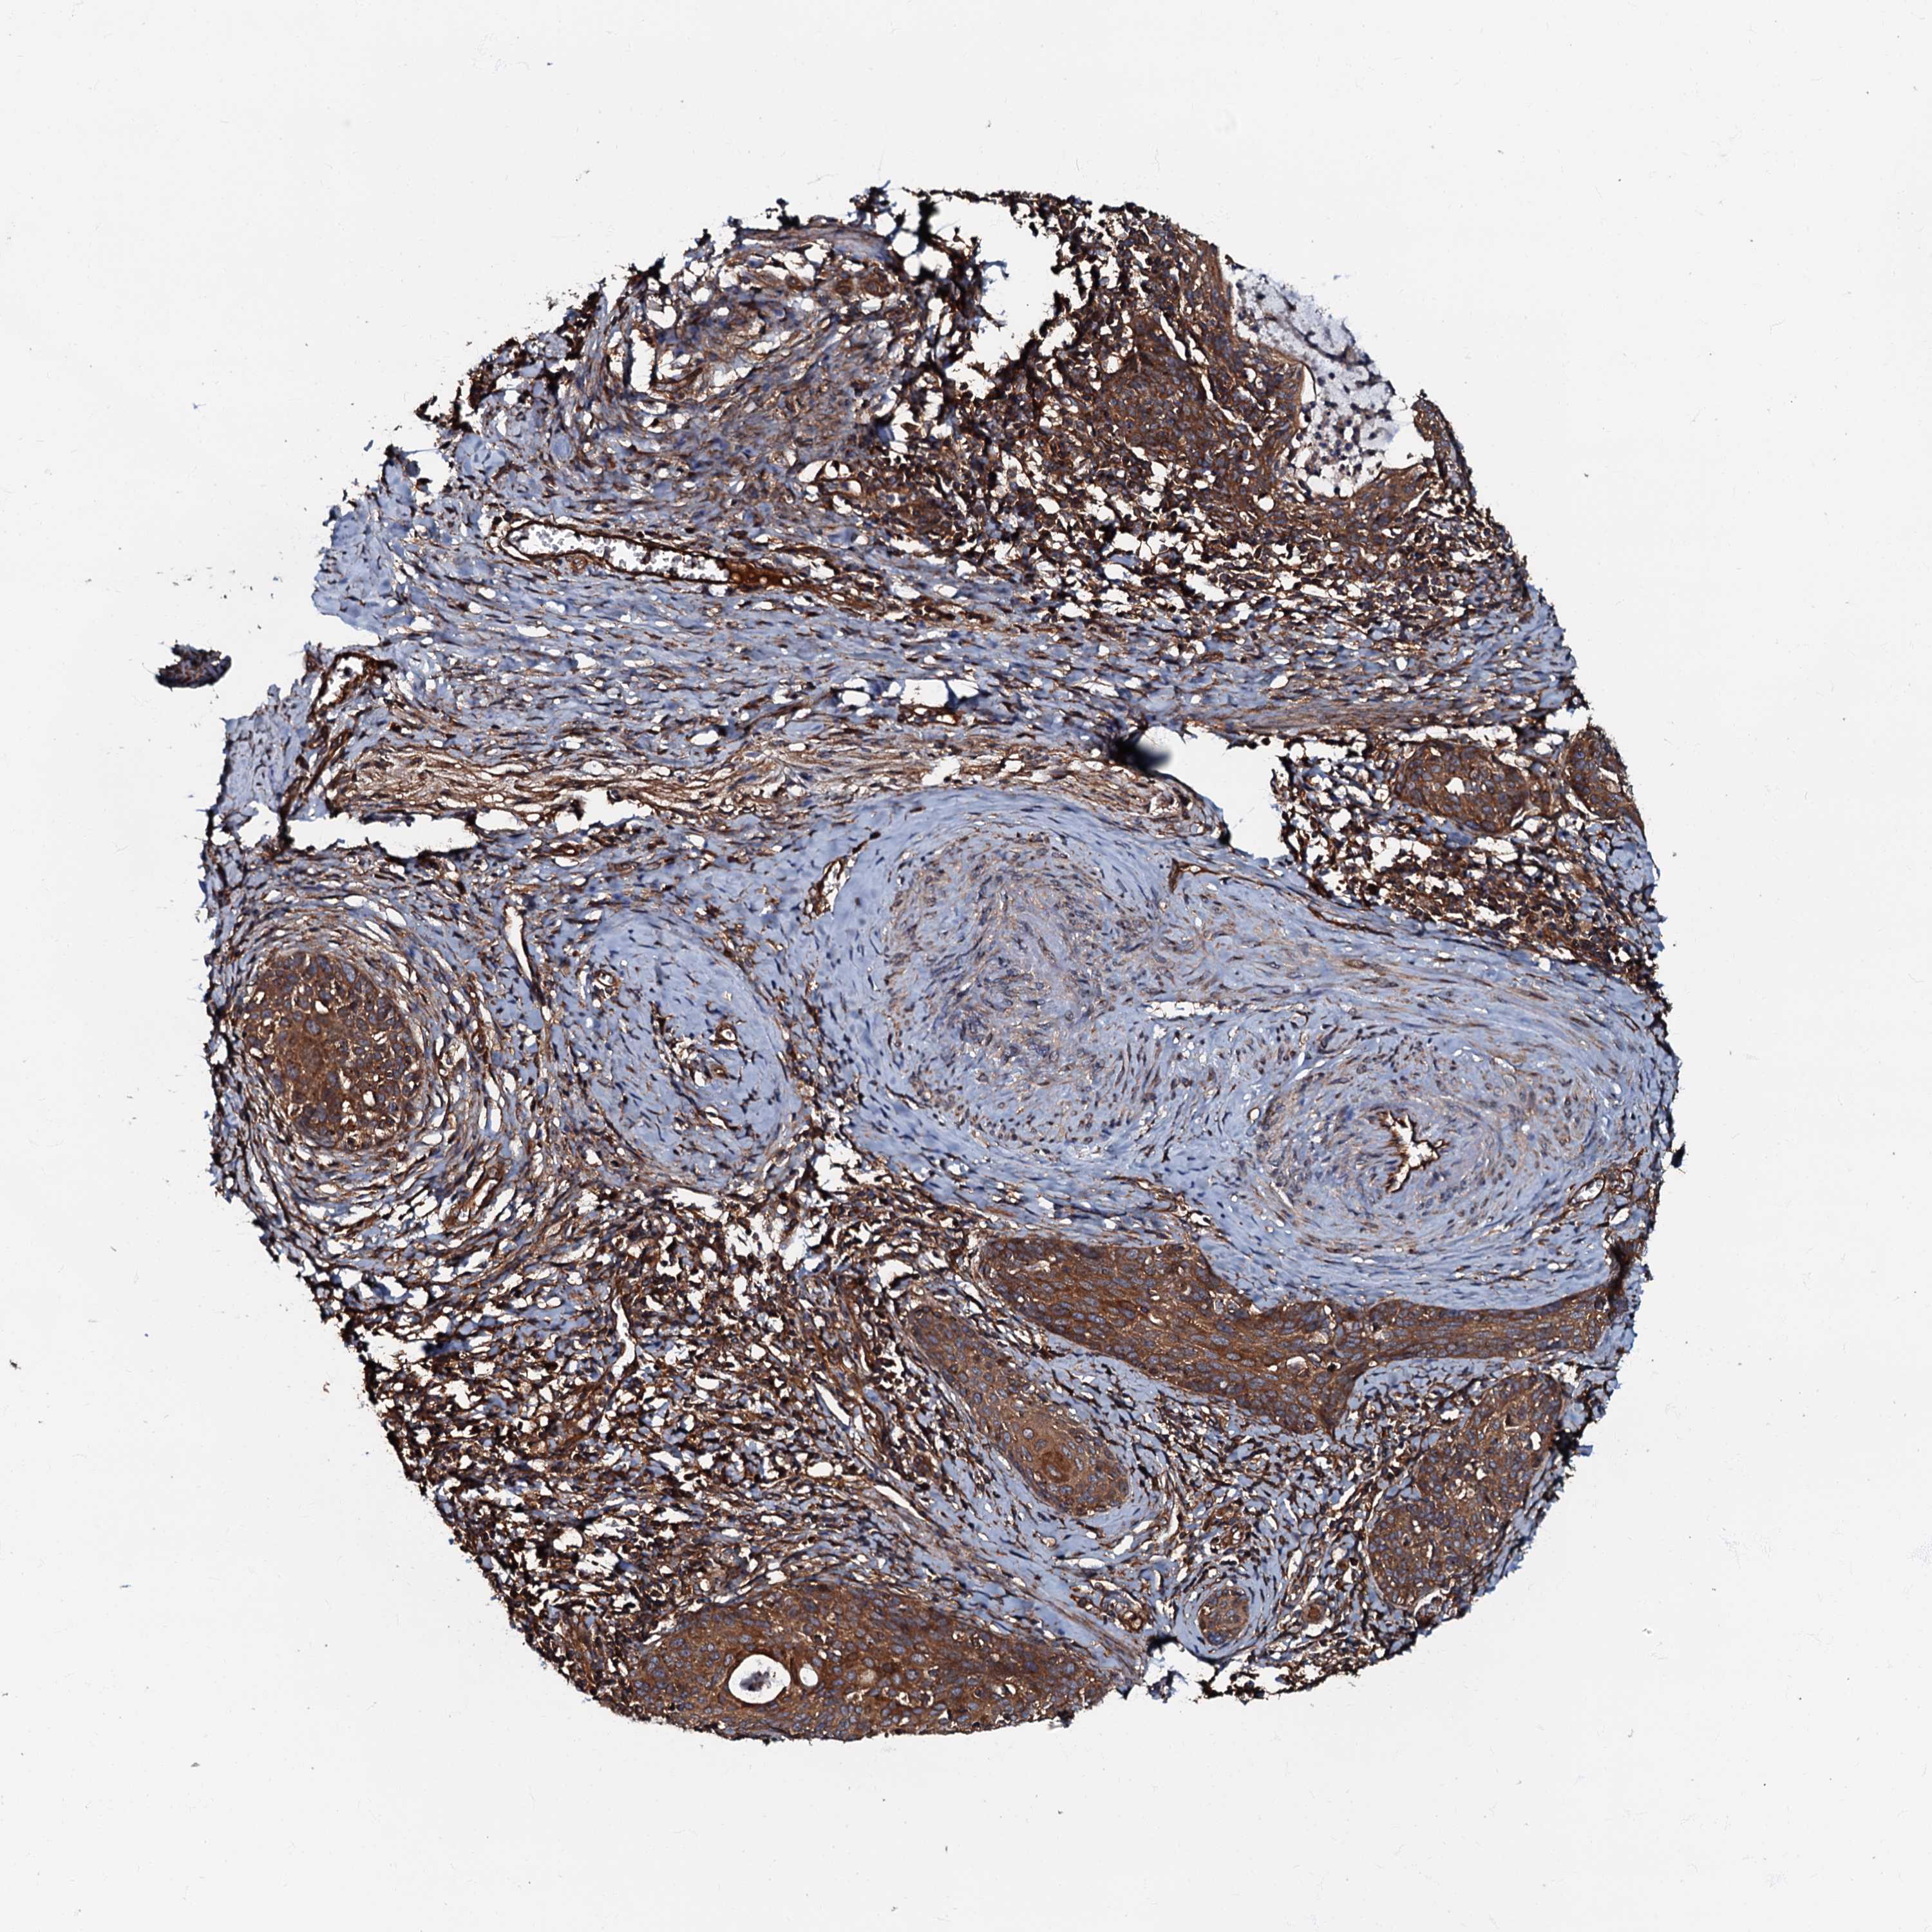

CERVICAL CANCER - Protein expressioni

A mouse-over function shows sample information and annotation data. Click on an image to view it in a full screen mode. Samples can be filtered based on level of antibody staining by selecting one or several of the following categories: high, medium, low and not detected. The assay and annotation is described here.

Note that samples used for immunohistochemistry by the Human Protein Atlas do not correspond to samples in the TCGA dataset.

Antibody stainingi

Antibody staining in the annotated cell types in the current human tissue is reported as not detected, low, medium, or high, based on conventional immunohistochemistry profiling in selected tissues. This score is based on the combination of the staining intensity and fraction of stained cells.

Each image is clickable and will lead to virtual microscopy that enables deeper exploration of all samples and also displays staining intensity scores, fraction scores and subcellular localization as well as patient and tissue information for each sample.

Antibody HPA039928

Staining

High

Medium

Low

Not detected

Intensity

Strong

Moderate

Weak

Negative

Quantity

>75%

75%-25%

<25%

None

Location

Nuclear

Cytoplasmic/membranous

Cytoplasmic/membranous,nuclear

Squamous cell carcinoma, NOS

Adenocarcinoma, NOS